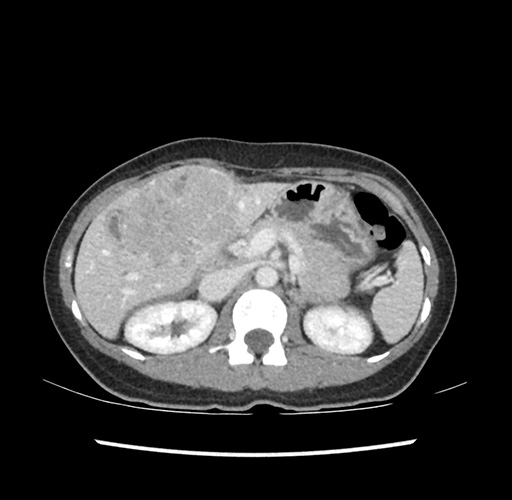

Imaging Analysis

Look through the patient's CT scan to identify any areas of concern for the necessary procedure.

Based on your CT findings, which issue(s) would give reason for "planned slowing down moment(s)" in this case?

Considering a standard left lateral sectionectomy procedure, what step(s) of the operation would you do differently in this case ?